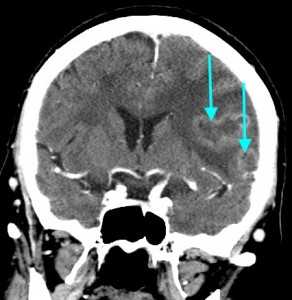

Метастазы головного мозга, фото. На КТ с контрастным усилением у пожилой пациентки (в верхнем ряду слева) с жалобами на головные боли выявлены множественные объемные образования в левом полушарии мозга, интенсивно накапливающие контрастное вещество. Образования имеют характерную форму в виде «кольца». На изображениях в нижнем ряду и вверху справа определяются множественные очаги в головном мозге: отчетливо видны округлые образования с более плотным «ободком» по периферии, располагающиеся в левой теменной доле.